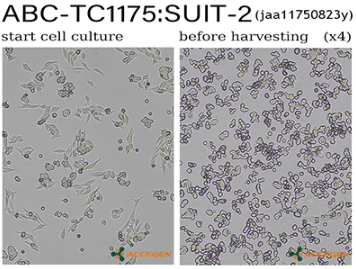

SUIT-2

ABC-TC1175

SUIT-2 is a human pancreatic cancer cell line derived from a liver metastasis of moderately differentiated tubular adenocarcinoma in a Japanese male patient. The cells exhibit an epithelial-like morphology with two distinct subpopulations under phase-contrast microscopy: one spindle-shaped and elongated, the other polygonal and epithelial. SUIT-2 cells express several pancreatic ductal markers including carcinoembryonic antigen (CEA), carbohydrate antigen 19-9 (CA19-9), CSPG2/versican, and Mac25/angiomodulin. Electron microscopy confirms features of pancreatic ductal epithelium. Karyotype analysis shows aneuploidy, consistent with malignant transformation. SUIT-2 cells are tumorigenic and metastatic, capable of forming tumors and spreading to regional lymph nodes in nude mouse xenografts.